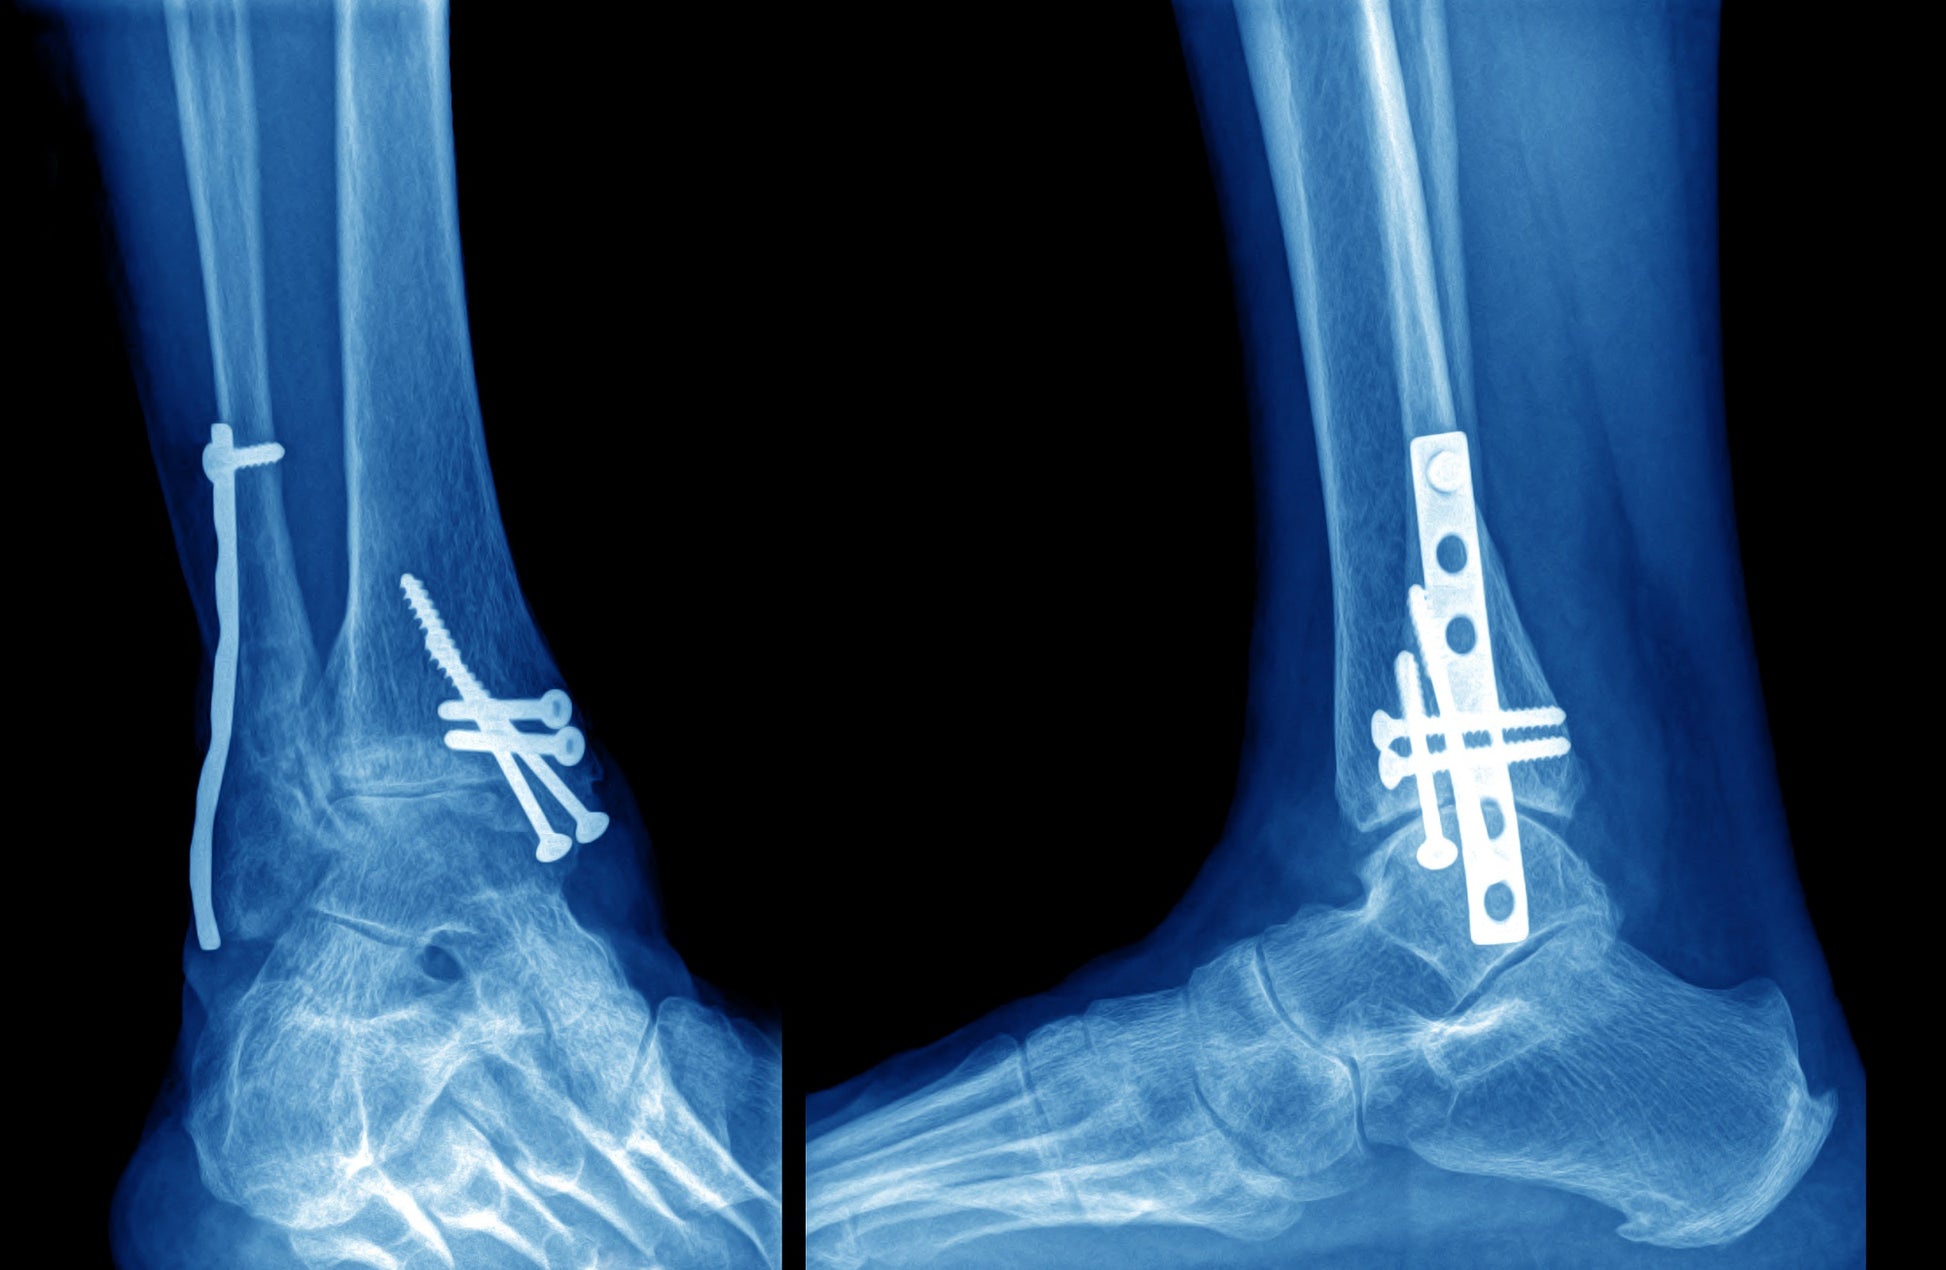

Set in early October 2017, this case follows Utz Claassen, the founder and chairman of Syntellix – a medical parts company that specialised in the research, development and sales of bio-absorbable, metallic implants. Syntellix was founded in 2008 as a spin-off from the special research division at the University of Hanover in Germany with the intention of translating the institute’s theoretical knowledge of magnesium-based biodegradable implants into viable medical applications. After the successful completion of animal testing in 2010, the company began human clinical studies of its patented MAGNEZIX® alloy used in compression screws, pins and plates for the treatment of bone fractures, which had traditionally relied on steel and titanium parts.

After more than five years of meticulous hard work, by 2017 MAGNEZIX® medical screws and pins have met CE-approval for human use in 30 countries. The product officially launched in Germany in September 2013. And by the end of 2016, about 25,000 successful implants had taken place across Europe, Asia, Africa and the Middle East. In March 2017, Syntellix AG founded Syntellix Asia based in Singapore, where it received venture financing and government support to make inroads into the booming Asian healthcare sector. Despite such success, the biggest operational difficulty Syntellix has is to continue making its way in a market dominated by gigantic players with huge resources, infrastructure and relationship network.